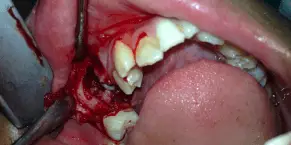

SURGICAL EXTRACTION OF IMPACTED PRIMARY MOLAR

A 8 year old boy reported to the department with a complaint of missing teeth in the lower left back teeth region. While recording the history his mother reported that the tooth in that region had not erupted. On clinical examination an edentulous space was seen and the first permanent molar had inclined towards this edentulous space. An OPG and IOPA were taken that showed the presence of an impacted primary second molar. Underlying it was a developing permanent 2nd molar. A surgery was performed for the removal of this impacted tooth which was followed by placement of a space regainer to distalize the permanent 1st molar.